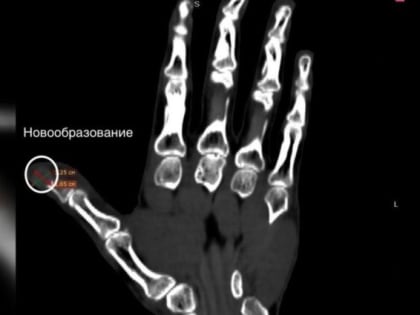

Фото пресс-службы ВОКБ №1. Опухоль на пальце левой руки 47-летнего пианиста удалили хирурги Воронежской областной клинической больницы №1.